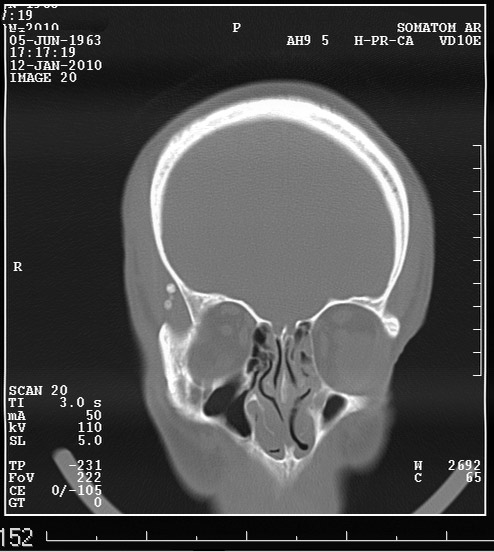

Ну вот деталь, которая может быть немаловажной - у пациента подагра, имеются тофусы в ушных раковинах.

Выкладываю данные КТ

На снимке утолщение веретенообразное мышечного слоя с наличием кальцификатов(два) Кальцификаты в мышце чаще встречаются при паразитарных инфекциях(трихиниллез,токсоплазмоз,цистецеркоз),но их больше по количеству и в разных местах.Оссифицирующий миозит-имеет свою картину и распространение.Насчет Хортона-навряд ли,это же поражение сосуда.Насчет тофусов-они содержат ураты,чаще локализуются подкожно(не в мышце),при подагре осификации вдоль сухожилий.А может был удар,гематома с частичной кальцификацией?

Если в анамнезе подагра, то тогда я за скопление солей уратов. Эта гадость может накапливаться где угодно, я сам видел и смотрел публикации коллег, когда это тофусы и в брюшной полости находили, а уж в мягких тканях, так это и подавно. Тем более что это болит, кальцинированная гематома не болела бы.

Плотность не соответствует дроби, она более денсная и даёт артефакты.